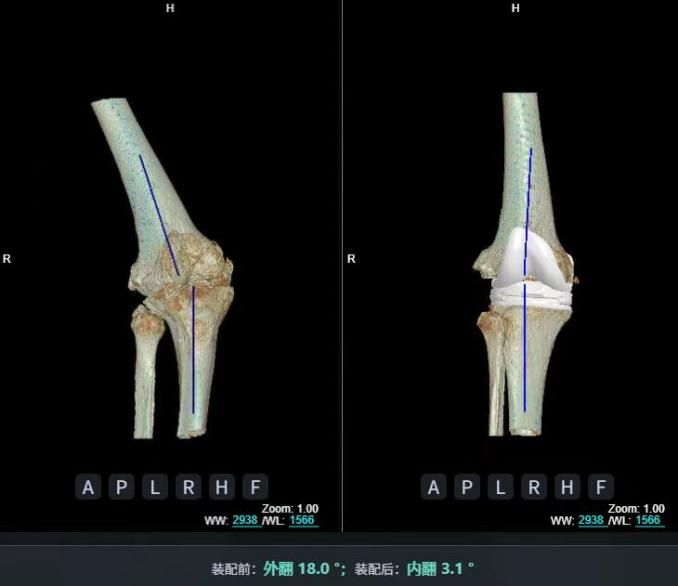

4.2 APTT-HTO脛骨高位截骨術

2025年7月,貴州醫科大學附屬醫院骨科團隊原創研發的腘肌前結節中脛骨高位截骨保膝術(Anterior Popliteus Transtibial Tuberosity-High Tibial Osteotomy, APTT-HTO)及其提出的脛骨結節分區與腘肌保護理論,登上了國際頂尖學術舞臺。該成果在全球最具影響力的專業會議之一——日本骨科協會第98屆年會上進行了兩次學術發言。[8]

該手術具有經皮微創、保留原生膝關節結構、符合階梯治療原則等優勢,通過調整下肢力線可促進部分軟骨再生,術后關節功能接近正常(如下蹲、爬山),患者還能從事中重體力勞動。相比其他術式,其有效規避了髕骨低位、血管損傷、合頁骨折等潛在并發癥。

目前,APTT-HTO技術已成功應用于千余名患者,幫助保留自身膝關節。此類保膝手術適用于單間室膝關節炎患者(如 “羅圈腿”),核心是通過調整力線糾正畸形,減輕磨損間室壓力、發揮健康間室作用,延長膝關節壽命。若出現膝關節疼痛、保守治療無效且X線顯示關節間隙部分狹窄,建議及時就醫評估是否適合手術。